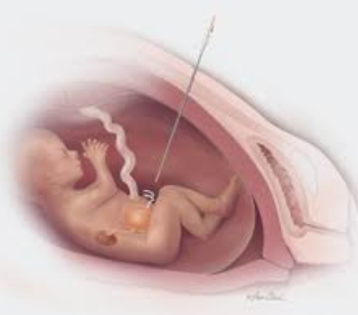

Fetal Blood Transfusion

Fetal blood transfusion, also known as intrauterine transfusion (IUT), is a medical procedure performed during pregnancy to treat certain conditions in which the fetus has blood